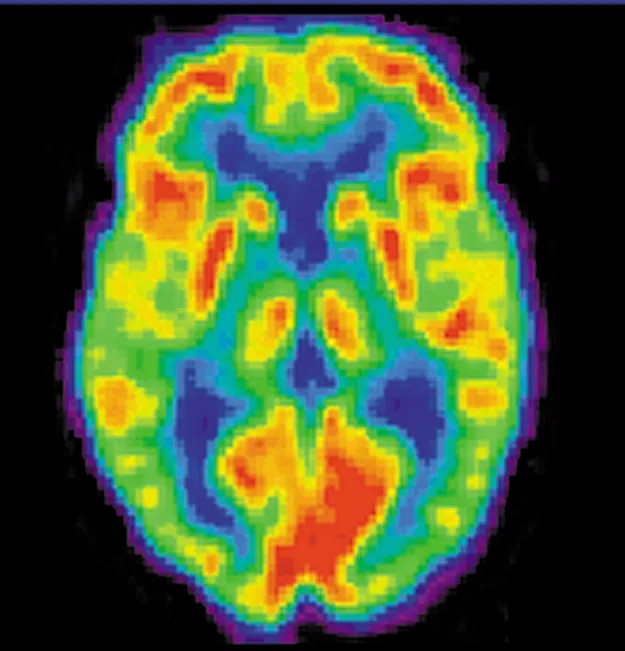

A brain scan. Different regions of the brain are shown in different colors.

Figure 32.2 A radiopharmaceutical is used to produce this brain image of a patient with Alzheimer’s disease. Certain features are computer enhanced. (credit: National Institutes of Health)

A host of medical imaging techniques employ nuclear radiation. What makes nuclear radiation so useful? First, γγ radiation can easily penetrate tissue; hence, it is a useful probe to monitor conditions inside the body. Second, nuclear radiation depends on the nuclide and not on the chemical compound it is in, so that a radioactive nuclide can be put into a compound designed for specific purposes. The compound is said to be tagged. A tagged compound used for medical purposes is called a radiopharmaceutical. Radiation detectors external to the body can determine the location and concentration of a radiopharmaceutical to yield medically useful information. For example, certain drugs are concentrated in inflamed regions of the body, and this information can aid diagnosis and treatment as seen in Figure 32.2. Another application utilizes a radiopharmaceutical which the body sends to bone cells, particularly those that are most active, to detect cancerous tumors or healing points. Images can then be produced of such bone scans. Radioisotopes are also used to determine the functioning of body organs, such as blood flow, heart muscle activity, and iodine uptake in the thyroid gland.